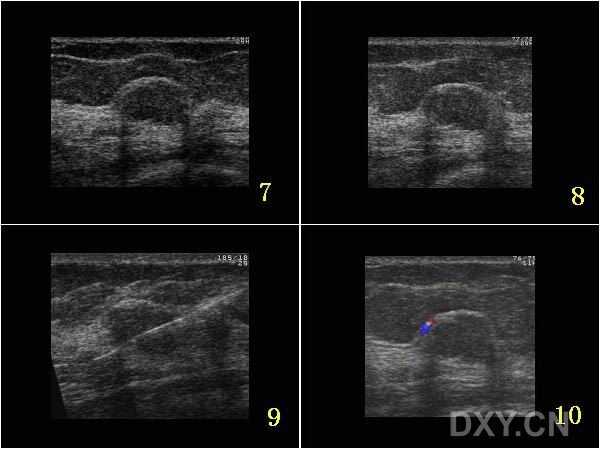

所以,第一步的“数据清洗”就成了苦活累活。好消息是,现在有了像BUSClean这样的开源工具来帮忙-7。它能像一位细心的质检员,自动识别并过滤掉那些无效的图像(比如大片黑的),把带有彩色血流标记、弹性成像等特殊模式的图像分门别类,还能智能地识别并裁剪出超声扫描的有效区域,把医生手绘的测量卡尺和文字注释提取出来-10。这就好比在把五湖四海的方言翻译成标准普通话,为后续的AI学习打下了坚实的基础。

对于诊断环节,AI能提供实时的辅助。例如,迈瑞的启元超声大模型能在医生扫查时,实时框检出疑似病灶并给出特征提示,自动完成测量,甚至能模拟专家的诊断思维链,生成结构化的报告草稿-6。北京协和医院的实践表明,这类技术能将BI-RADS诊断的准确性提升5%-10%-6。这对于提升基层医生的诊断信心和水平、促进不同医院间诊断的同质化,意义重大-9。

更有意思的是,AI病例库还能在医疗资源紧张时扮演“智能分流员”的角色。一项来自美国纪念斯隆·凯特琳癌症中心的研究提供了生动案例-8。在新冠疫情导致大量患者随访延误的时期,医院对221个“可能良性”(BI-RADS 3类)的结节重新用AI进行评估。AI成功地将其中两个最终确诊为癌的结节标记为“可疑”,敏感度达到100%-8。虽然它也会将一些良性结节标记为可疑(假阳性),但在特殊时期,它能有效地帮助医生优先召回风险最高的患者,确保最需要的人得到最及时的处理-8。这展示了一种超越单纯诊断判断的、基于风险的动态管理能力。